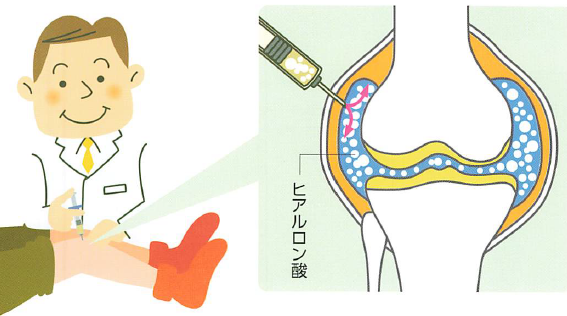

5. ヒアルロン酸注射

「痛みを和らげる」「動きを滑らかにする」効果に加え、近年ではヒアルロン酸注射が関節軟骨の保護や変形の進行抑制に役立つ可能性が研究で示唆されています。

Q. グルコサミンやコンドロイチンは効果がありますか? A. 現在のところ、医学的な効果は明確には証明されていません。当院では、より効果の期待できるヒアルロン酸注射などを推奨しています。